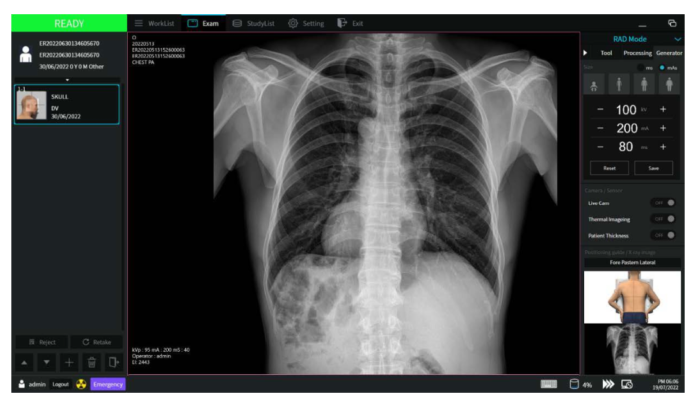

Radiography

🔹 Simple workflow

🔹 Emergency exam

🔹 Image preview

🔹 Fast image processing time (<0.8 sec)

🔹 Advanced image processing

ExamVue™ DTS Suite

An extension of ExamVue™ Duo ecosystem

The exclusive software for StriXion™ offers Live Video X-ray (fluoroscopic images), X-ray images, and tomographic images in one package. Built upon the same intuitive and powerful ExamVue™ Duo software used in all JPI systems, the Strixion™ software gives you complete control over x-ray acquisition, technique and diagnosis.

DR Acquisition

Live Video X-ray

2D Slice Viewer

Dynamic Flat Panel Detector

ExamVue PACS

DICOM Modality Worklist